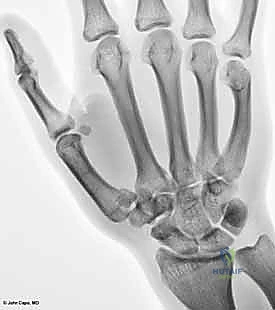

البنية العظمية للمفصل (The Bony Anatomy)

يتكون هذا المفصل من التقاء قاعدة عظم المشط الأول للإبهام (First Metacarpal Bone) مع العظم المربعي (Trapezium) الموجود في صف عظام الرسغ. يُصنف هذا المفصل من الناحية التشريحية على أنه "مفصل سرجي حقيقي" (Saddle Joint). هذا يعني أن الأسطح المفصلية لكلا العظمين تتخذ شكلاً مقعراً في اتجاه ومحدباً في الاتجاه الآخر، مما يسمح لها بالتشابك التام.

التصنيف الدقيق لأنواع كسور مفصل الإبهام

يُعد التحديد الدقيق لنوع الكسر الخطوة الأهم في تحديد مسار العلاج. كخبير متمرس، يقوم الأستاذ الدكتور محمد هطيف بتصنيف هذه الكسور بعناية فائقة لضمان اختيار التدخل الأنسب. تُقسم هذه الكسور بشكل رئيسي إلى كسور داخل المفصل (Intra-articular) وكسور خارج المفصل (Extra-articular).

1. كسر بينيت (Bennett's Fracture)

هو أشهر أنواع كسور قاعدة الإبهام وأكثرها تعقيداً. وهو كسر داخل المفصل يتميز بوجود خط كسر مائل يفصل شظية صغيرة من الجانب الراحي الزندي (Volar-Ulnar) لقاعدة المشط الأول.

2. كسر رولاندو (Rolando's Fracture)

تم وصفه لأول مرة بواسطة الطبيب سيلفيو رولاندو. وهو كسر مفتت داخل المفصل (Comminuted Intra-articular Fracture).

* يأخذ خط الكسر غالباً شكل حرف "Y" أو "T"، مما يعني أن قاعدة عظم المشط تنقسم إلى ثلاث قطع أو أكثر.

3. الكسور خارج المفصل (Extra-articular Fractures)

هي كسور تحدث في قاعدة عظم المشط الأول ولكنها لا تمتد إلى السطح المفصلي مع العظم المربعي.

* تكون إما كسوراً مستعرضة (Transverse) أو مائلة (Oblique).

* نظراً لأنها لا تؤثر على الغضروف المفصلي، فإن خطر الإصابة بخشونة المفاصل المستقبلية يكون أقل بكثير، وغالباً ما تستجيب بشكل ممتاز للعلاج التحفظي (التجصيص) إذا لم يكن هناك انحراف زاوي كبير (Angulation).